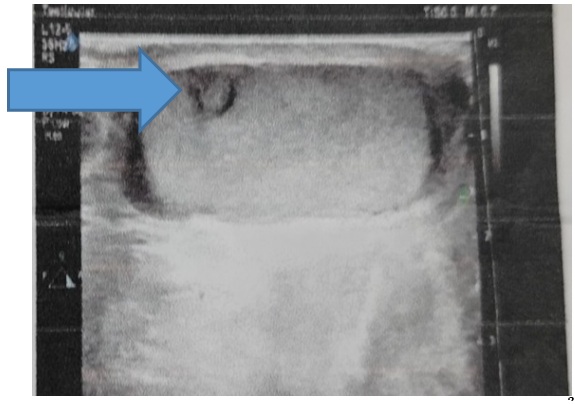

Bệnh nhân được chỉ định siêu âm Doppler bìu để đánh giá tổn thương.

Kết quả siêu âm cho thấy:

• Tinh hoàn hai bên kích thước trong giới hạn bình thường

• Tại cực trên tinh hoàn trái có cấu trúc tăng âm nghi dị vật kim loại kích thước khoảng 2,7 mm

• Xung quanh có dấu hiệu tổn thương nhu mô tinh hoàn

Kết quả này cho thấy dị vật kim loại đã xuyên vào nhu mô tinh hoàn, cần được xử trí sớm để tránh các biến chứng như nhiễm trùng, hoại tử mô tinh hoàn hoặc ảnh hưởng chức năng sinh sản.

Hình 1. Hình ảnh siêu âm Doppler bìu xác định vị trí tổn thương nhu mô tinh hoàn.